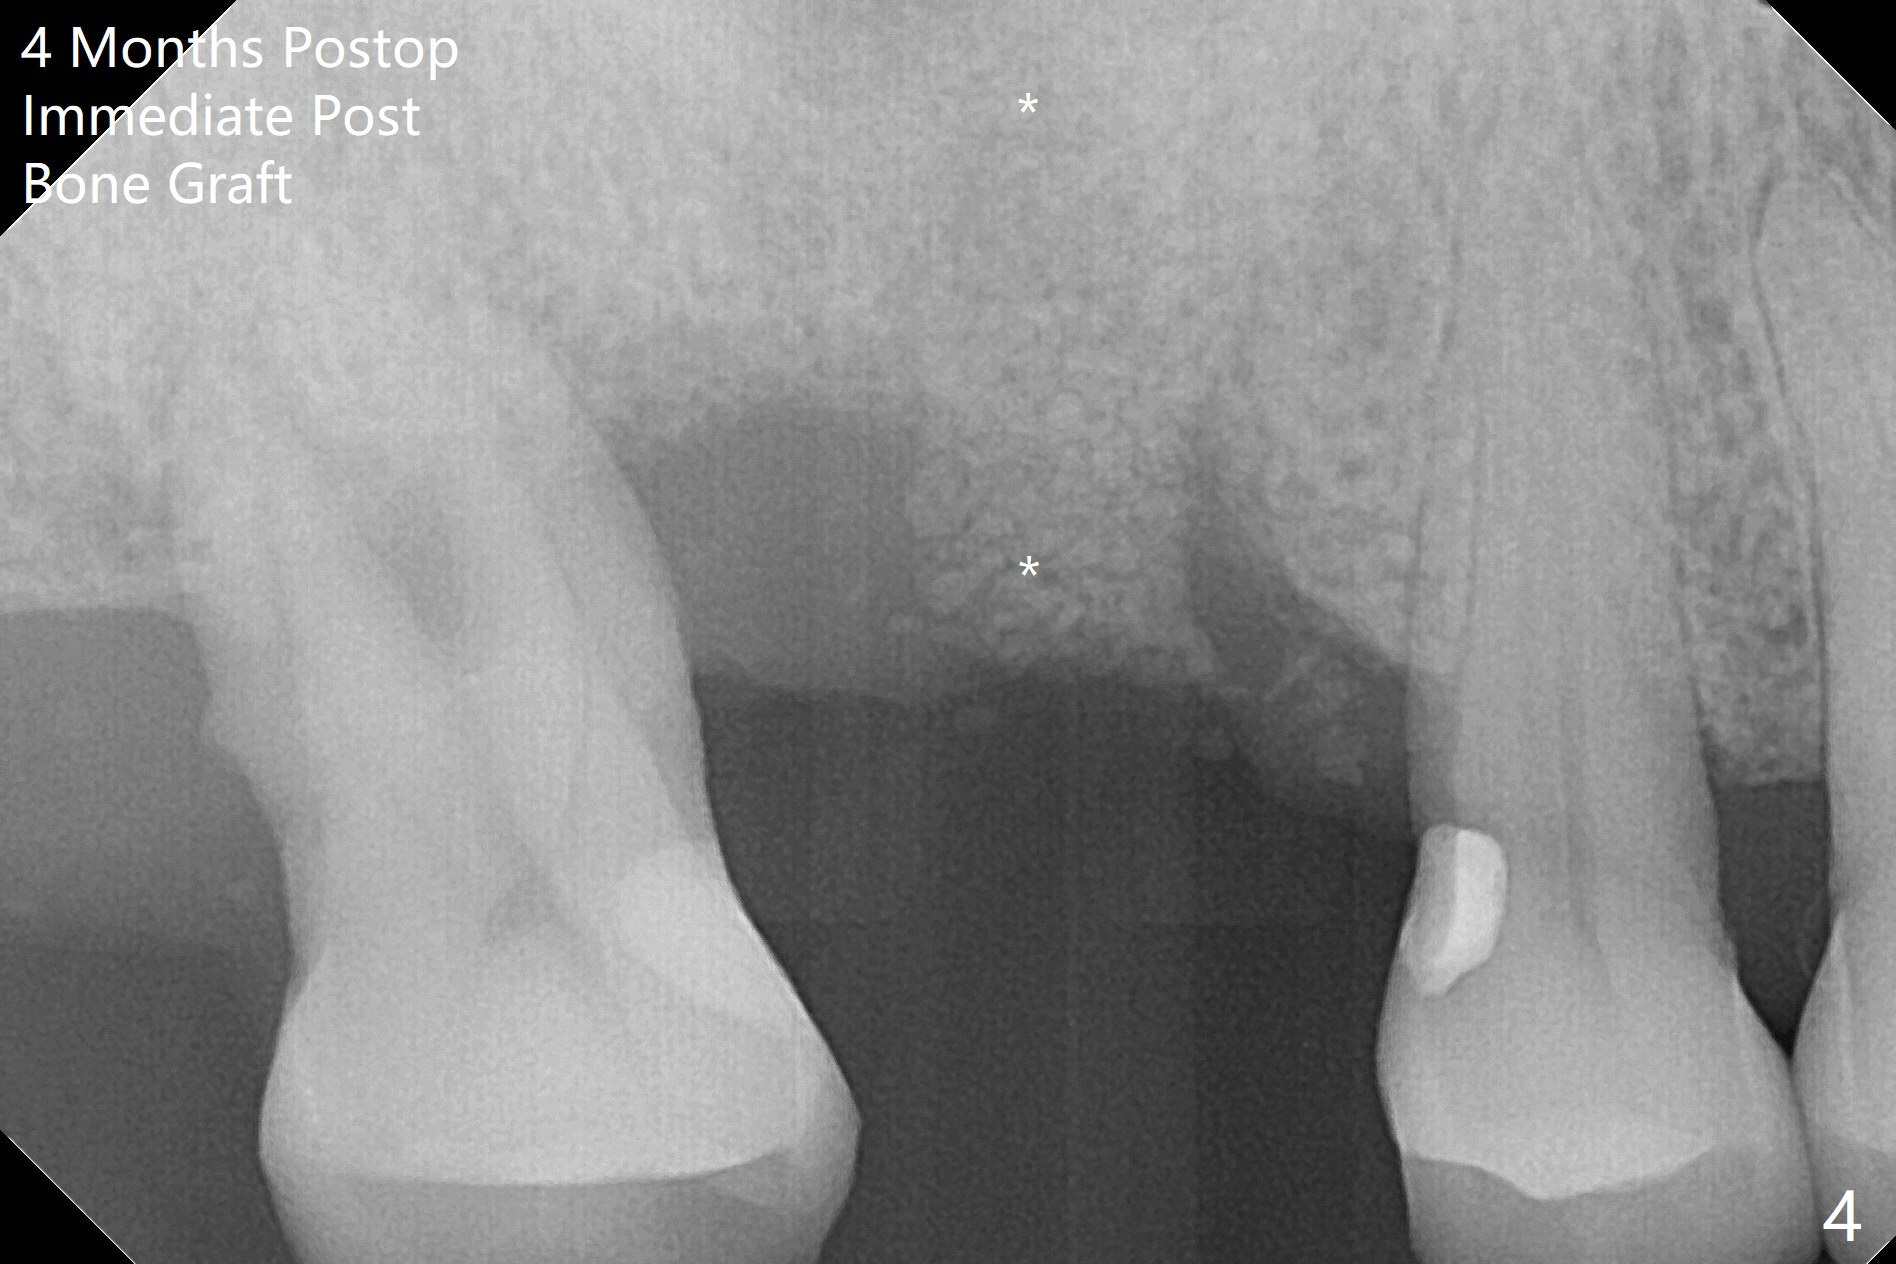

使用来自钻头的自体骨做提升,植体植入后,颊侧骨板薄,刚好骨下。使用5.5毫米profile drill后,放置愈合基台,术后三个月脱落,他再次要求修复,甚至提出退款,不愿意回诊所,因为他有糖尿病,新冠病毒高危人群。 放置小号愈合基台(图二)。他原来托牙是Valplast,没有occlusal rests,不能经过修改临时使用,可能将直接放置修复基台做临时牙冠。放置修复基台后(图三(术后三个月)),制作临时牙冠时,发现前者有些松动,后者就没有粘固。当基台完全就位,它最冠方与植体没有间隙(箭头),根方有间隙(空心箭头)。其实愈合基台也是一样(图一,二)。后来植体松动(术后4个月),拔除,植骨(图四),颊侧骨板缺失(图五:B)。植骨后5个月2号牙疼痛需要拔除种植(图七),与3号牙一起种植(图六),颊侧骨板修复,但是高度有所下降(箭头)。The narrow ridge with the intact buccal plate (Fig.8 >) can hold a 4x8.5 mm implant. The buccal plate is lost 4 months postop (Fig.9) and restores 5 months post graft (Fig.10). Return to Upper Molar Immediate Implant, No Deviation Coronal and Apical Gap in IBS implant Protect Graft Xin Wei, DDS, PhD, MS 1st edition 06/22/2020, last revision 05/02/2021